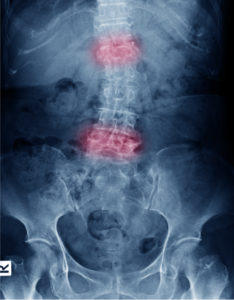

Low Back Pain

Low back pain can be disabling; however, most cases heal with time (2-12 weeks) and with conservative therapy. Surgery is suggested…